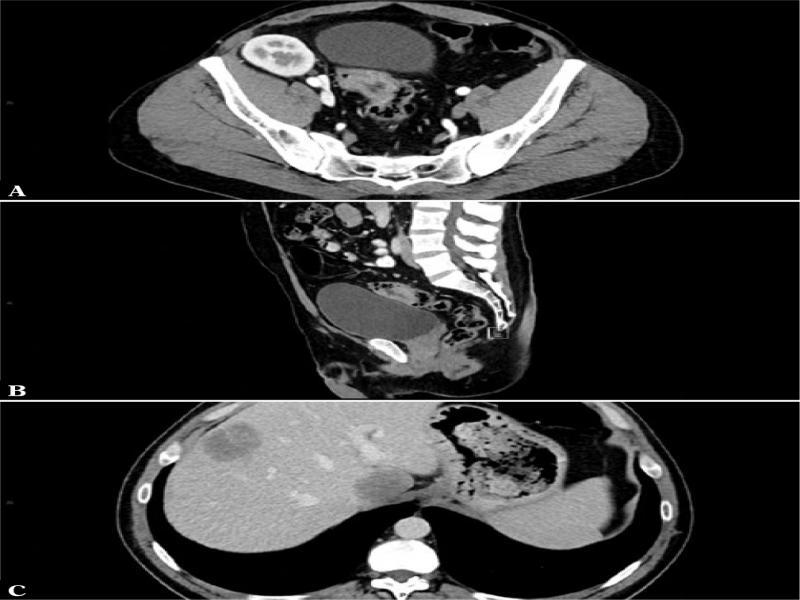

Fig. 2.